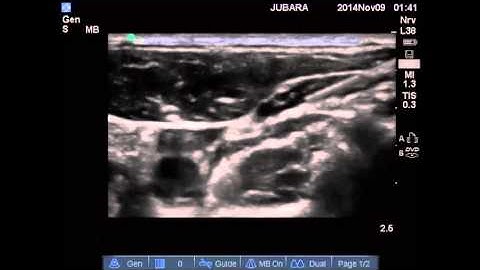

Intermediate Cervical Plexus Block